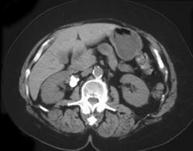

问题 男,68岁,偶然发现高血压,请根据所示图像,选择最可能诊断 ( )

选项 A、右肾血管瘤 B、右侧肾上腺嗜铬细胞瘤 C、右肾囊肿合并出血 D、右肾动脉瘤 E、右肾出血

答案 D